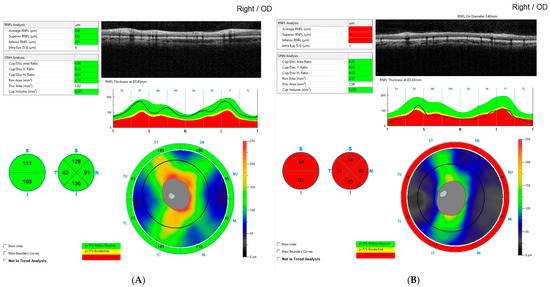

Correlation Between Endocrine and Other Clinical Factors with Peripapillary Retinal Nerve Fiber Layer Thickness After Surgical Treatment of Pediatric Craniopharyngioma

Background: Visual dysfunction resulting from damage to the optic nerve and retinal neurons represents a significant concern in the postoperative management of childhood-onset craniopharyngioma (CP) survivors. The study aims to evaluate the influence of clinical parameters assessed in patients before and after [...] Read more.

Background: Visual dysfunction resulting from damage to the optic nerve and retinal neurons represents a significant concern in the postoperative management of childhood-onset craniopharyngioma (CP) survivors. The study aims to evaluate the influence of clinical parameters assessed in patients before and after neurosurgery of CP on peripapillary retinal nerve fiber layer (RNFL) thickness results, using optical coherence tomography (OCT) as early markers of compressive neuropathy. Methods: This study retrospectively examined 73 eyes from 38 individuals diagnosed with CP and 64 eyes from 32 healthy controls matched for age and sex. All patients in the study group underwent a complete endocrine examination before and after surgery. Moreover, all participants in both groups underwent a thorough ophthalmological examination and OCT imaging. The average RNFL thickness was analyzed, along with the RNFL in the superior and inferior sectors and in eight peripapillary sectors around the optic nerve. Clinical variables were analyzed to assess how they relate to alterations in RNFL thickness within specific sectors. Results: After surgery, the peripapillary RNFL thickness was much lower in the CP group than in the healthy control group. Preoperative factors significantly affecting RNFL reduction are as follows: age below 5 years at the time of diagnosis, birth in the country, optic disc oedema, delayed puberty, arginine vasopressin deficiency (AVD), growth hormone deficiency (GHD), hyperprolactinemia, and the degree of preoperative hypothalamic involvement. Moreover, syndrome of inappropriate secretion of antidiuretic hormone (SIADH), as well as the end of AVD, memory disorder and hyperfagia after surgery, correlated with damage to RNFL. Conclusions: CP causes significant thinning of the RNFL, which demonstrates the tumor’s impact on the visual pathway. Monitoring optic nerve damage and assessing outcomes after surgery can be performed effectively using OCT. Additionally, the relationship between RNFL thickness in specific areas and clinical indicators can provide vital information for diagnosing and monitoring. This highlights their usefulness in forecasting visual results. As a result, ongoing RNFL assessments should be part of the long-term management of CP patients to improve visual outlook and identify ongoing or remaining damage. Full article

Figure 1